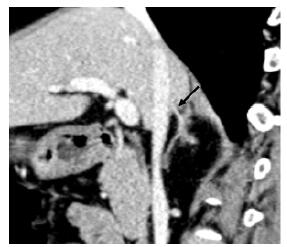

结果  以MIP或MPR技术评价图像质量, 左肾上腺静脉97例(97%)为1级, 1例(1%)为2级, 2例(2%)为3级; 右肾上腺静脉52例(52%)为1级, 19例(19%)为2级, 29(29%)例为3级。左肾上腺静脉均为1支; 91%与膈下静脉汇合后汇入左肾静脉; 左肾上腺静脉平均直径(3.6±0.6)mm(2.4~4.5 mm); 左肾上腺静脉与左肾静脉形成交角, 平均为(121.9±16.0)°(150~58°)。2例发现右侧双支肾上腺静脉; 67例(94%)右肾上腺静脉汇入下腔静脉, 4例(6%)汇入右副肝静脉; 右肾上腺静脉平均直径(3.2±0.5)mm(1.9~4.0 mm); 右肾上腺静脉与下腔静脉形成交角, 平均为(75.3±16.6)°(90~35°)。

Results  In the evaluation of image quality with MIP or MPR images, the left adrenal vein was excellent in 97% patients, sufficient in 1%, and non-diagnostic in 2%. For the right adrenal vein, 52% were excellent, 19% were sufficient, and 29% were non-diagnostic. The left adrenal vein was always a single one, 91% of which joined the inferior phrenic vein and then drained into the left renal vein. The diameter of the left adrenal vein ranged 2.4 mm to 4.5 mm (mean:3.6±0.6 mm). The angle of the left adrenal vein and left renal vein ranged 150° to 58° (mean:121.9±16.0°). Two patients were found to have double right adrenal veins. The right adrenal vein drained into the IVC in 67 of 71 patients (94%) and into the right accessory hepatic vein in 4 patients (6%). The average diameter of the right adrenal vein ranged 1.9 mm to 4.0 mm (mean:3.2±0.5 mm). The angle of the right adrenal vein and IVC ranged 90° to 35° (mean:75.3±16.6°).